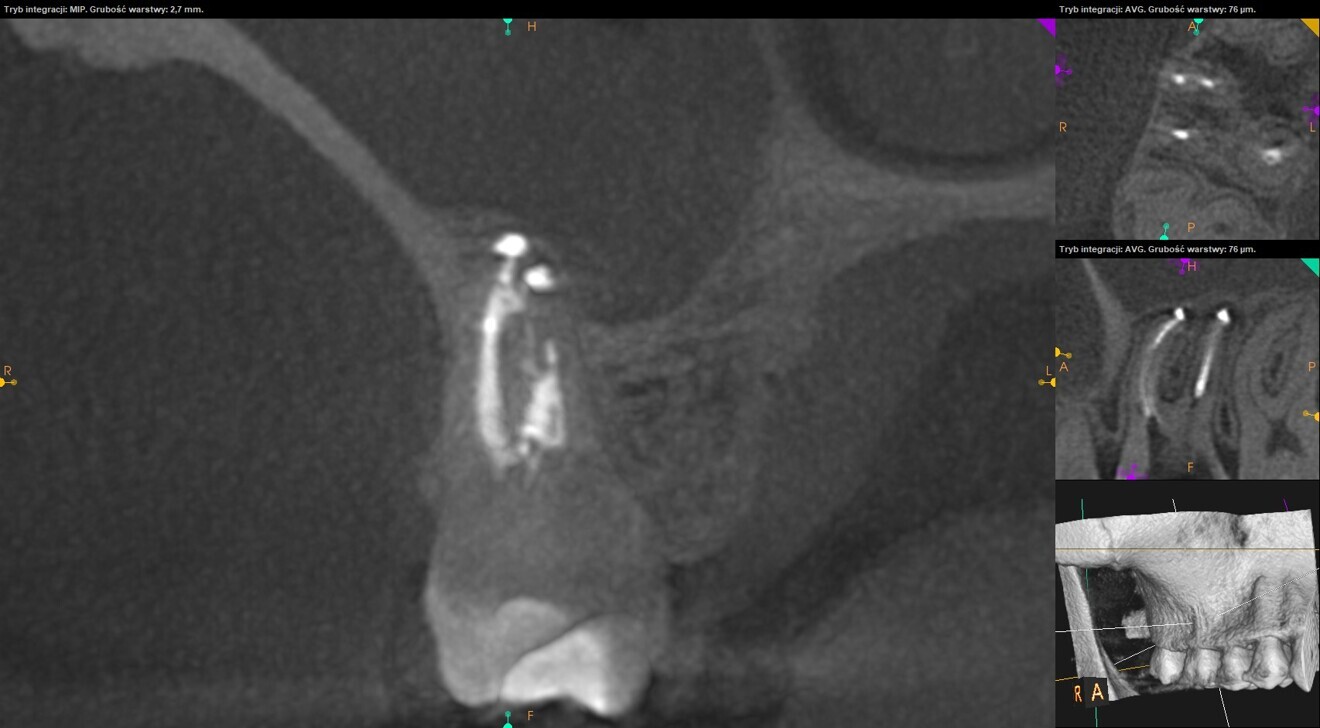

To confirm that the mesial root had been filled properly, the patient was referred for a CBCT scan. The examination revealed that the MB2 canal had been filled with the sealing material and that there was an isthmus between the MB1 and MB2 canals in the apical third of the root and two separate portals of exit (Fig. 14). The tooth was restored with composite resin, and the patient was referred for an indirect restoration with cusp coverage and scheduled for a recall appointment in six months.

At the recall appointment, the CBCT examination found no signs of inflammation. The tooth was asymptomatic, and the Schneiderian membrane was not enlarged (Fig. 15).

Fig. 14

Figs. 15a & b